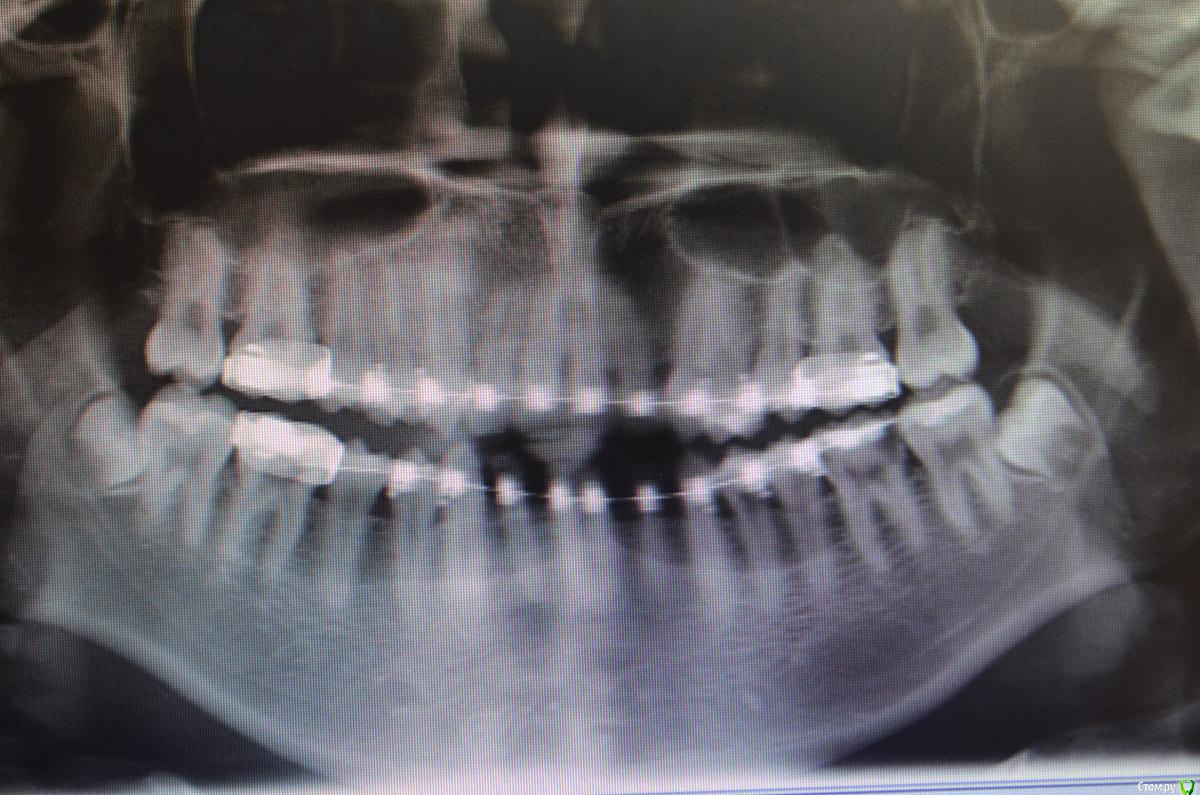

Пациентке 16 лет носила брекеты 4 года (переносила), нижний фронт зубов подвижен, слизистая воспалена, тремы на н.ч, множественный кариес под брекетами после снятия, сейчас на этапе эндолечения. Помогите советами как правильно и с чего начать , на в.ч. поставил ретейнер, на нижней пока идет терапевтическое лечение. ТРГ нету